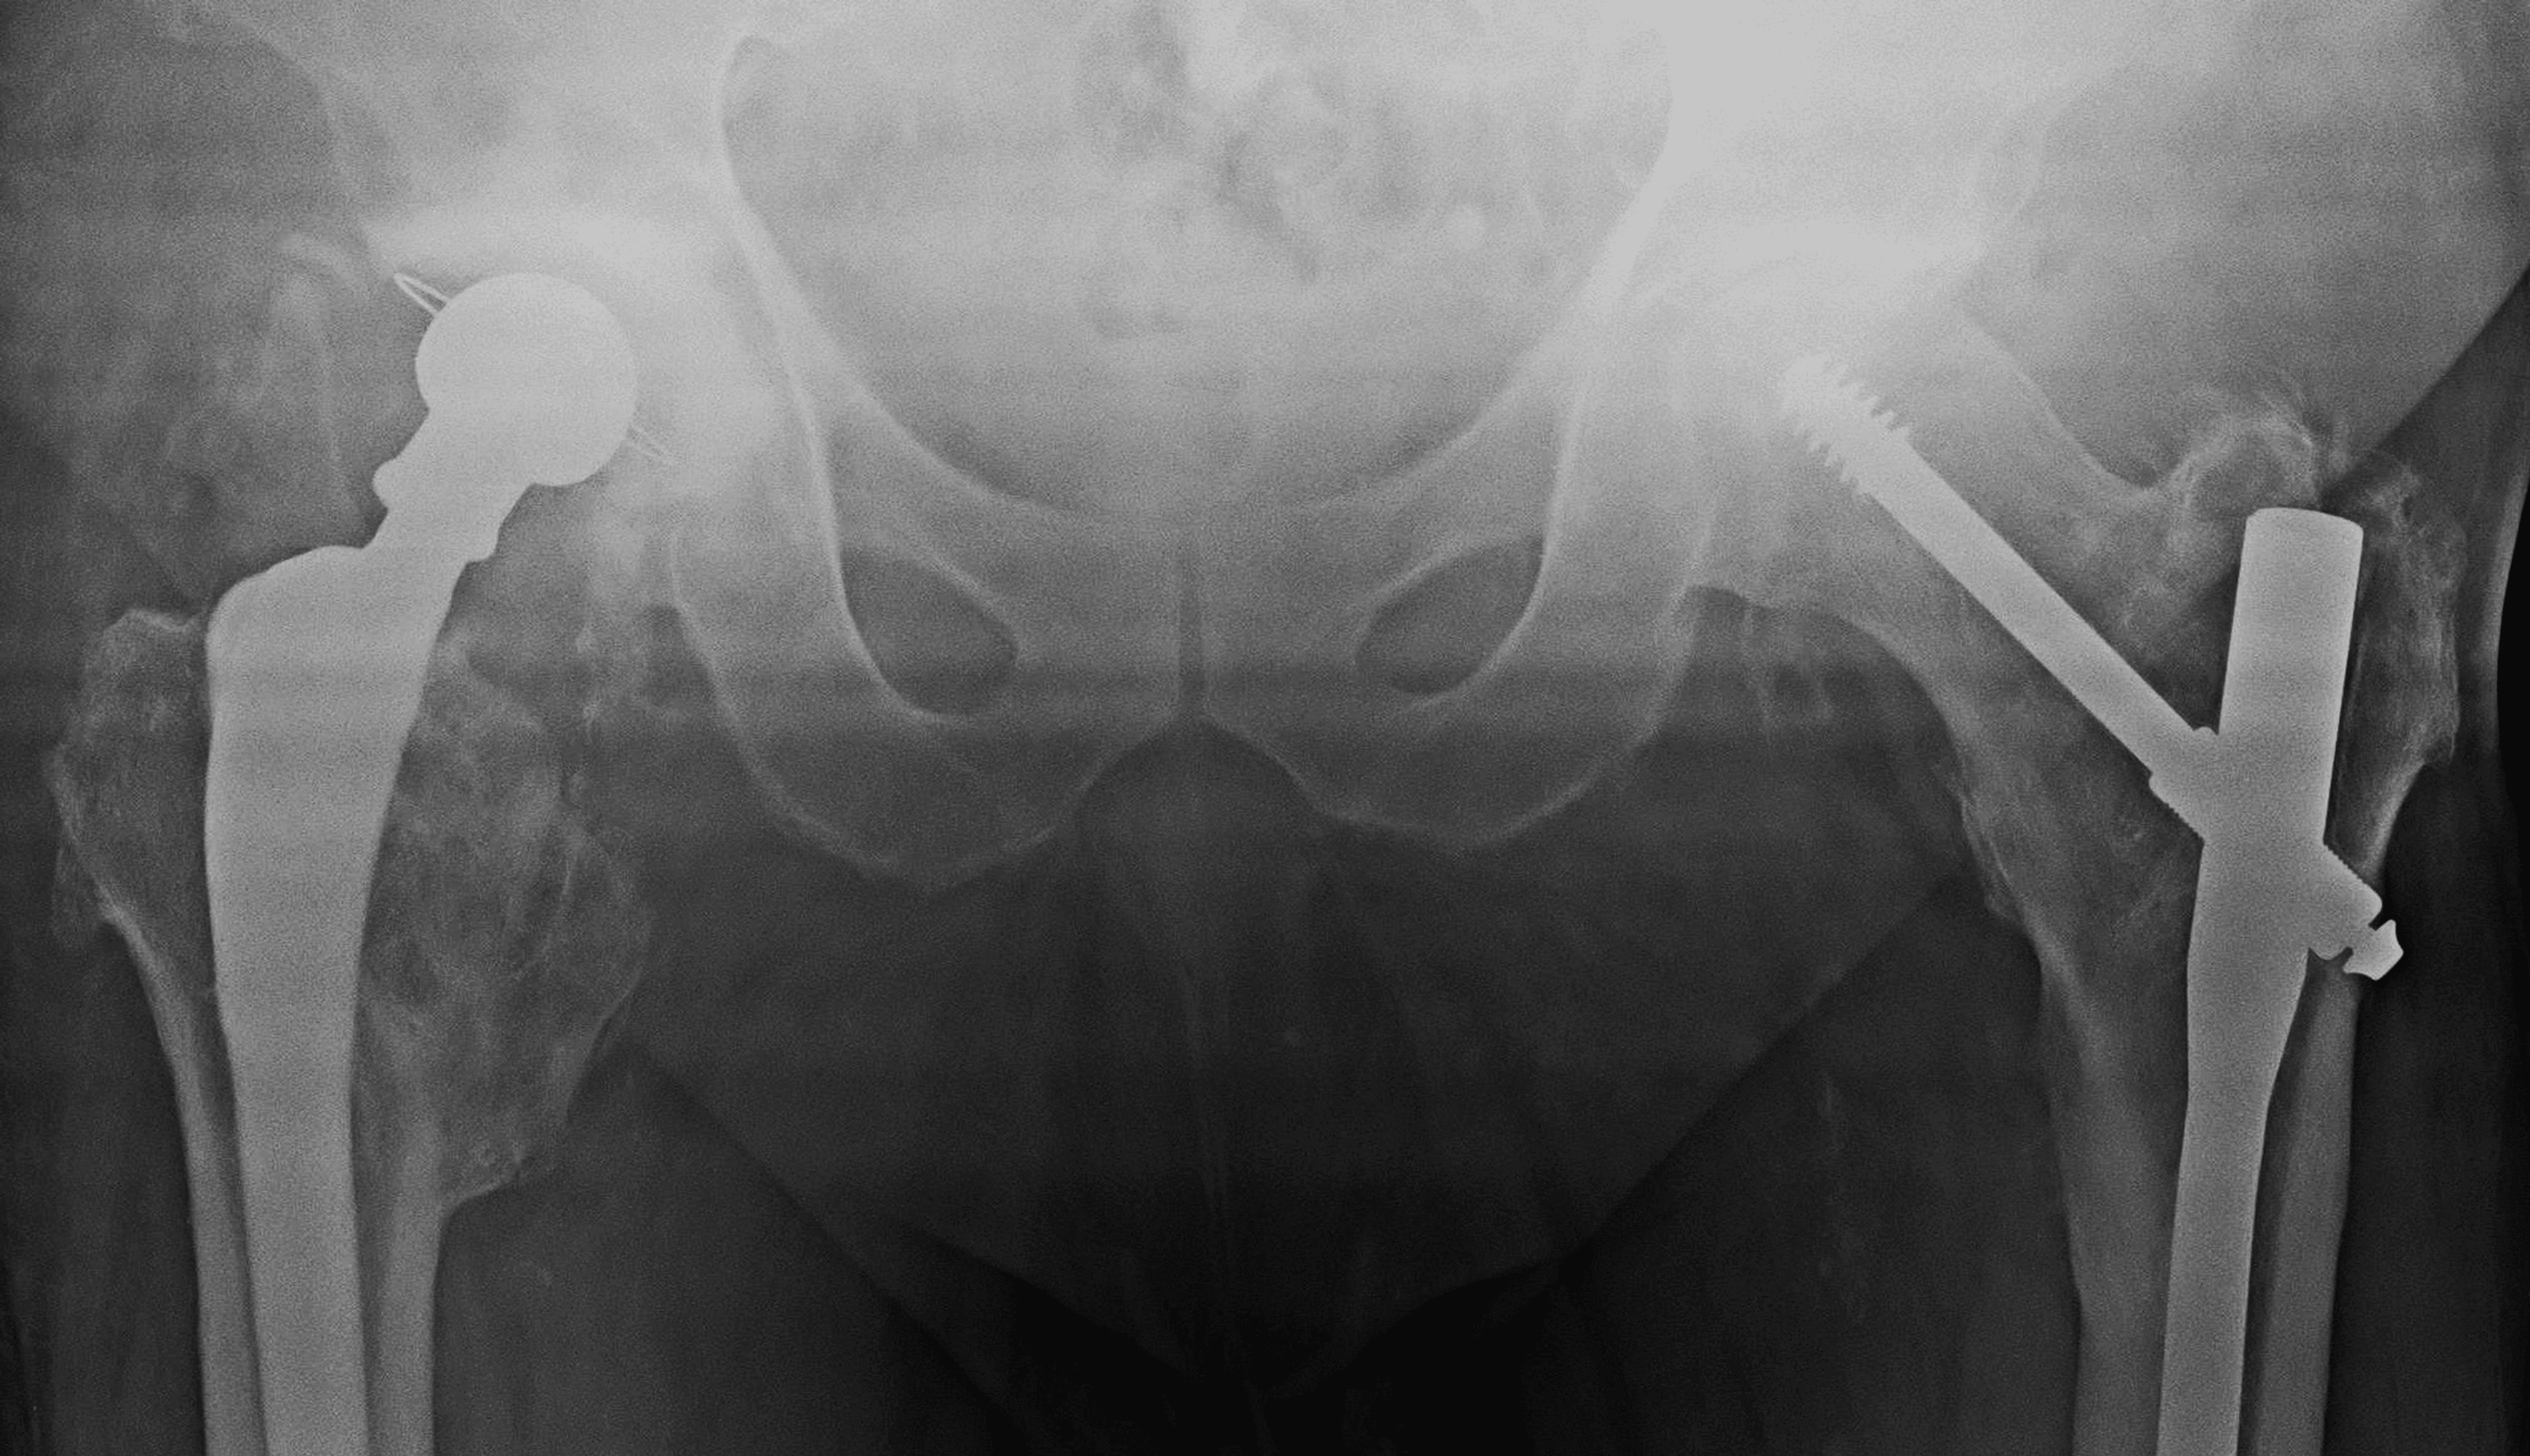

Fracture After Total Hip Replacement Orthopedic & Sports Medicine

Fracture After Total Hip Replacement Orthopedic & Sports Medicine Total Hip Replacement Dislocation Treatment Dislocation after total hip replacement. In this review, the types, causes, and treatment modalities of hip dislocation are discussed and illustrated, with particular emphasis on the assessment, treatment, and. Approximately two thirds of cases are successfully treated; The risk of dislocation after primary. One third of cases will require surgical treatment (e.g., revision. After a total hip replacement, you will. Total Hip Replacement Dislocation Treatment.